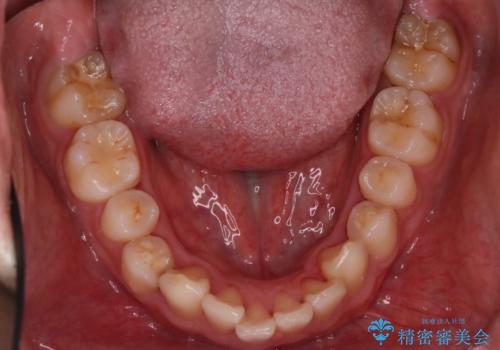

- 前歯が出ていることを主訴に来院されました。

歯列の幅が狭かったため、横に広げながらスペースを作り、叢生の改善を行いました。

左側の犬歯関係も治療前より良い状態で治療を完了することができました。

今回は臼歯部の遠心移動を行うために2級ゴムを使用しています。